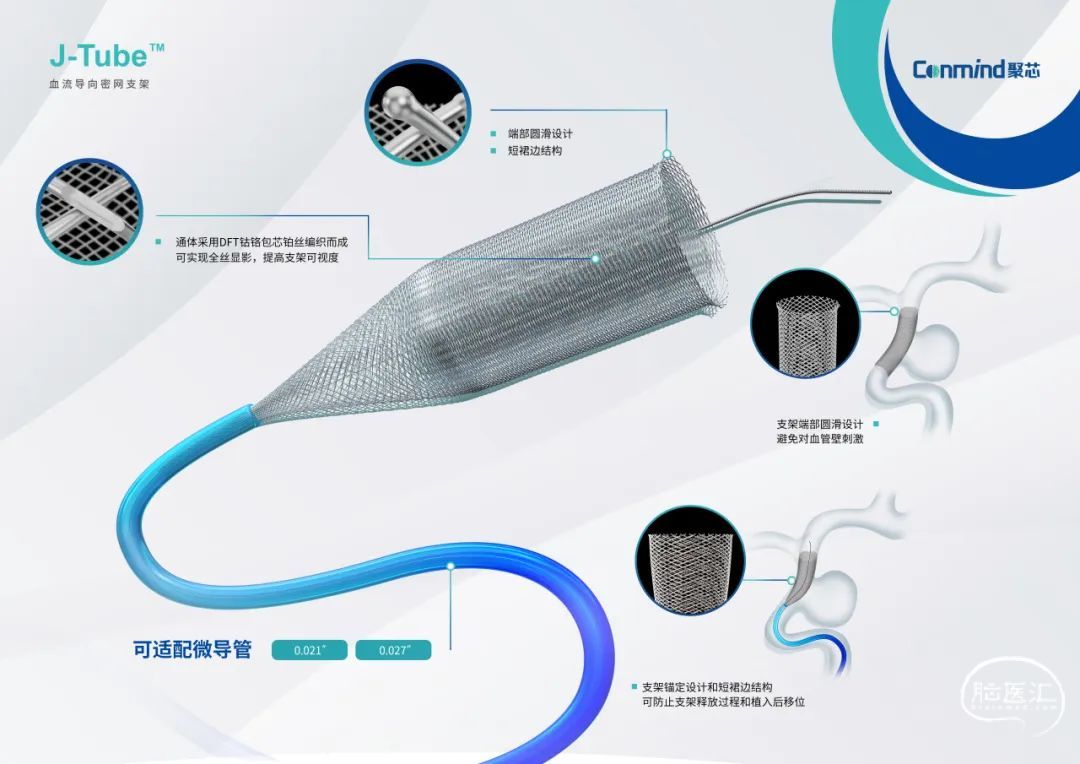

颅内动脉瘤是威胁人类健康的重大疾病之一,其治疗难度大、风险高。过去由于传统的治疗手段往往受限于技术与材料的不足,难以有效应对复杂多变的动脉瘤病变。J-Tube™血流导向密网支架的出现为颅内动脉瘤的治疗带来了新的曙光。其采用先进的材料与精密制造工艺,不仅在设计上更加贴合人体血管的生理结构,还通过优化的材料选择,提高了支架的生物相容性与耐久性。这种创新的支架系统,能够在复杂的血管环境中稳定工作,为颅内动脉瘤的治疗提供了更为可靠的保障。脑医汇-神介资讯平台联合聚芯医疗科技公司焕新推出“聚汇医声”动脉瘤血流导向治疗专栏,旨在分享J-Tube™血流导向密网支架最新使用经验、技巧。